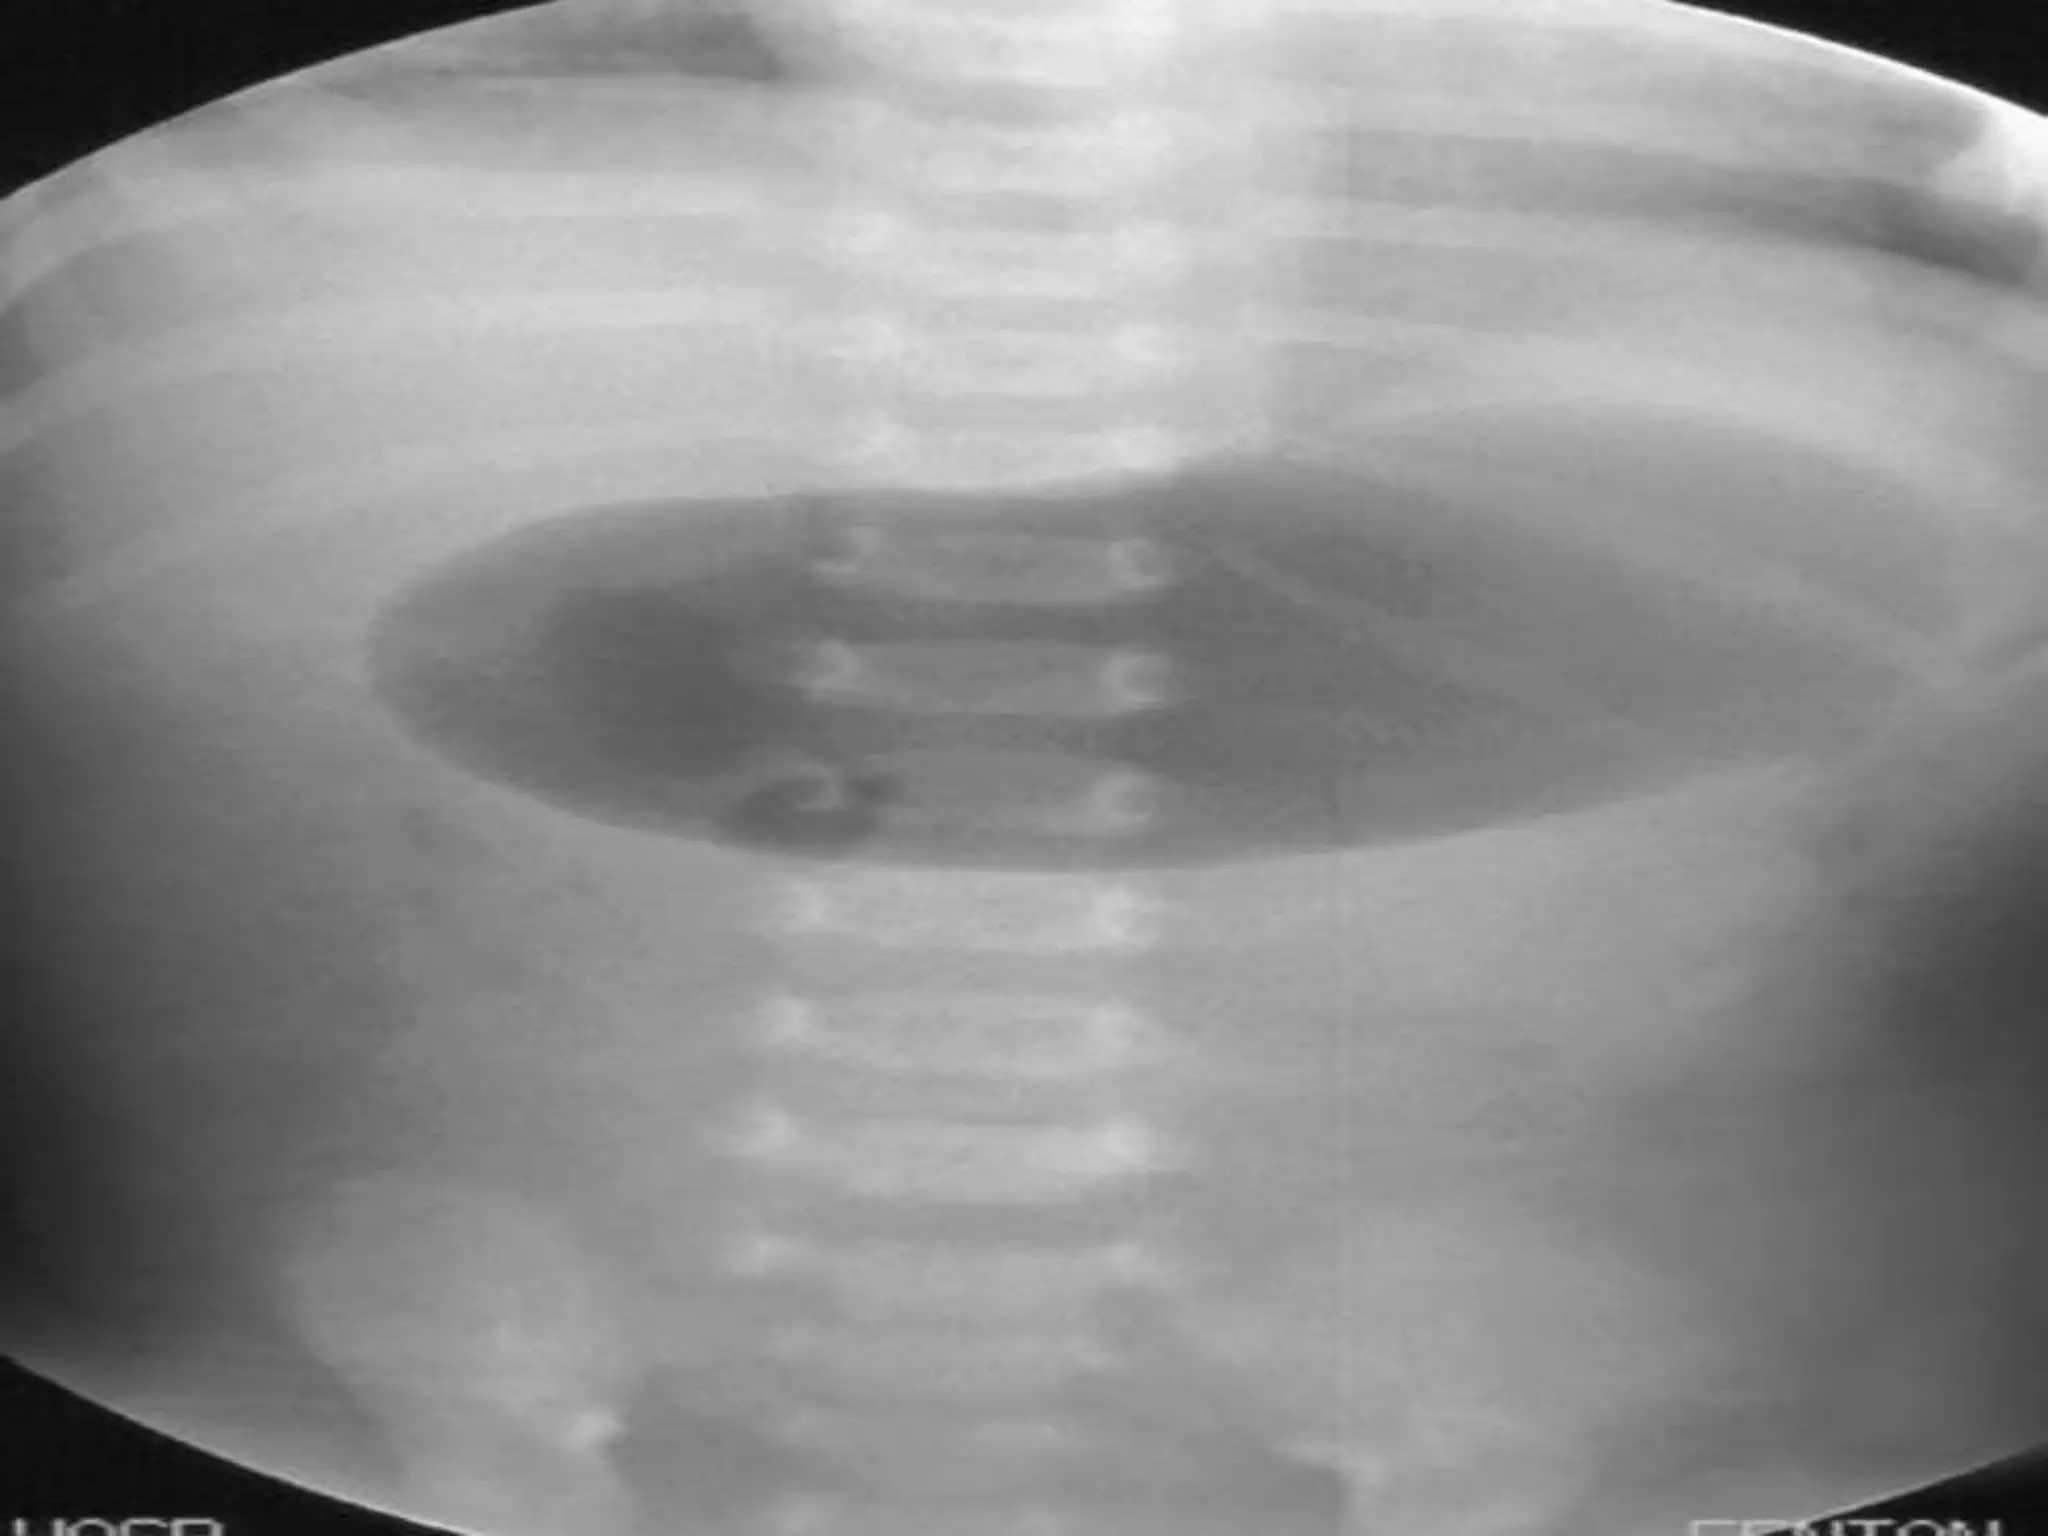

DIAGNOSIS

• Plain X-Ray.

• Doppler study.

• Upper contrast study.

• CT- scan.

DIAGNOSIS • Plain X-Ray. •Doppler study. • Upper contrast study. • CT- scan.